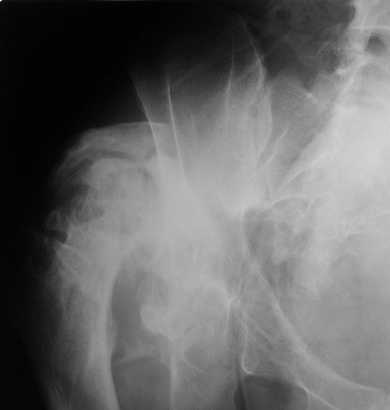

Уважаемые коллеги. Пациент 30 лет 3 года назад в результате травмы получил травматический дефект нижних конечностей до в/3 голеней, был пропущен вывих бедра.

В настоящее время очень неплохо ходит на протезах, движения в неоартрозе близки по объему к здоровой стороне. Основная жалоба - выраженная боль при ходьбе. планируем двухэтапное эндопротезирование - задним доступом мобилизовать проксимальный отдел бедра, резецировать шейку, аппаратом низвести бедро(головку оставить там где она есть, так как больших дефектов не видно(может пригодится в последующем?)). Вторым этапом бесцементное эндопротезирование. Насколько такой вариант реалистичен? Доступ для второго этапа? Может быть другие варианты?С уважением, Максим

На последнем срезе КТ задний край практически отсутсвует по сравнения со здоровой стороной. Разумеется, что это плоскостное изображение, но головка вывихнулась не только в плоскостную щель захваченную на КТ. Если вы считаете, что удастся установить туда чашку даже низкопрофильную, остается пожелать вам успехов. Но перед этим можно смоделировать установку чашки на скиаграммах КТ.

За пожелание успехов - спасибо, думаю это пригодится, не очень понял про плоскостную щель, специально предоставил срезы на уровне свода - он цел, дефект заднего края ниже, за счет заглубления он будет еще меньше, по данным 3d - должно получиться.

Низводить надо обязательно, лучше в аппарате и лучше без остеотомии.

Если в аппарате низводиться не будет, то из небольшого доступа, лучше под контролем С-дуги выполнить остеотомию шейки. Без предварительного

низведения максимально возможная коррекция длины - 2,5-3 см.

Доступ - по предпочтениям хирурга, я предпочитаю передний с расширенной задней мобилизацией.

Решение по ВВ придется принимать по месту.... Сумеете "подрыться" и получить хорошее покрытие чашки (+2 винта об-но) - хорошо, если нет -

костная аутопластика из головки.